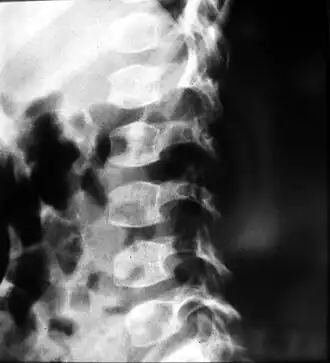

Diagnostische evaluatie voor SEDc omvat meestal een medische voorgeschiedenis en lichamelijk onderzoek. In verschillende expertisecentra worden verschillende tests gebruikt, zoals röntgenfoto's, MRI-scans, genetische tests, heuparthrografie, EOS-beeldvorming, visus- en gehoortests, en longfunctietests. Deze tests bieden een volledig beeld van de medische gezondheid van de patiënt en helpen bij het opstellen van een individueel zorgplan.[3]